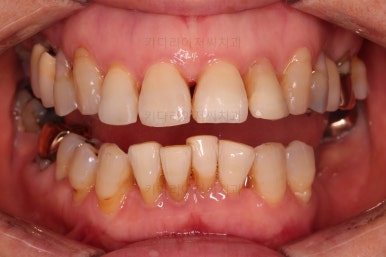

마무리 때의 사진입니다.

부산부분교정 전후사진을 비교해 볼게요.

치열이 매우 가지런해졌고 보이던 틈새도 다 없어졌으며 뻐드러진 느낌도 완벽히 좋아졌어요.

잇몸에서 쑤욱 빠져나와 보이던 치아도 원위치를 찾았고요.

앞니도 약간이나마 뒤로 들어가서 입매도 많이 좋아졌어요.